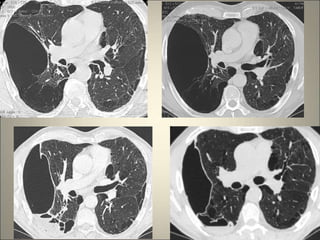

Atteinte des petites voies aériennes

• Signes de bronchiolite cellulaire : micro

nodules flous centro lobulaires , parfois

branchés (bronchioles centrolobulaires

dilatées et impactées par mucus, pus,.. )

• Poumon en mosaïque sans destruction de

l’architecture pulmonaire (obstruction

bronchiolaire inhomogène )